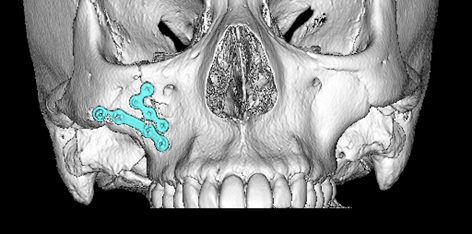

歯科インプラント治療は、顎骨にチタン製の金属(インプラント体)を埋め込み、その上に人工歯(上部構造)を装着することで咬合機能を回復する治療です。当科では、骨量が不足しており骨増生手術が必要な難症例に対しても、人工骨を使用することによって低侵襲に歯科インプラント治療を行います。CT検査を行い、手術シミュレーションソフトを用いた治療計画により、安全性の高い治療を提供します。

人工骨を用いて骨増生手術を行った歯科インプラント治療(左:術前、右:術後)

最新 骨補填材料&メンブレンYEARBOOK2021/2022 藤田記述箇所より引用